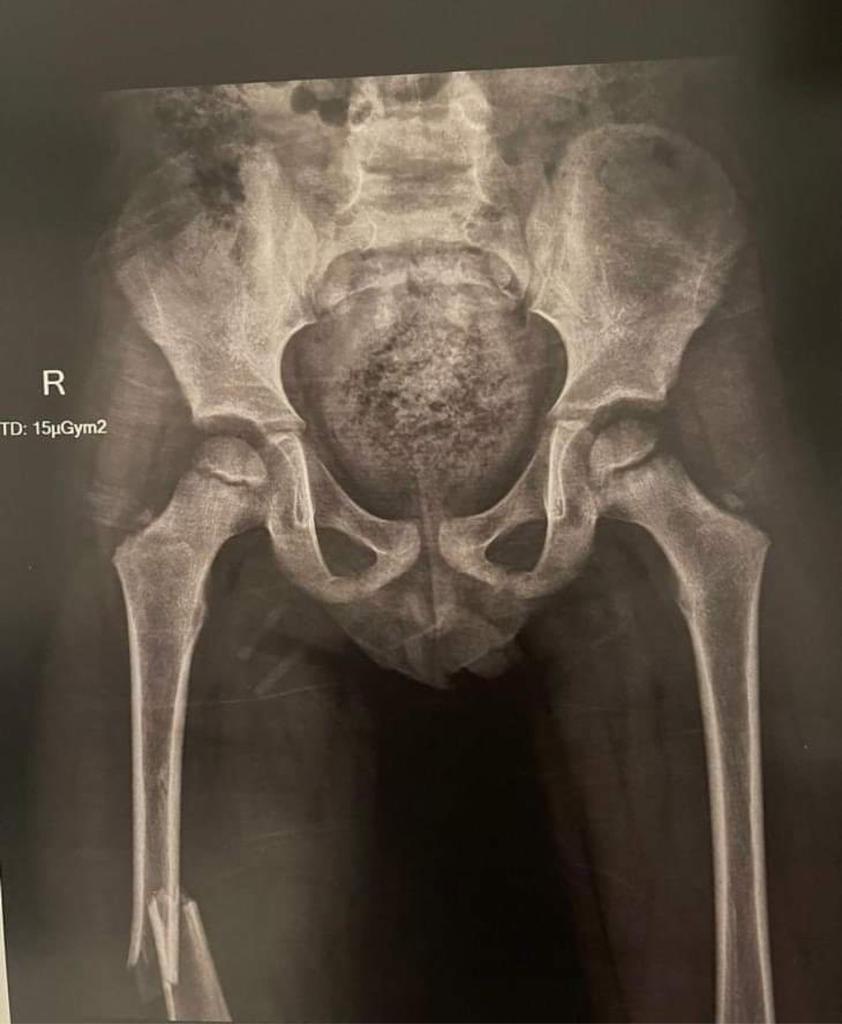

وقال والد الطفل أحمد فتحي لـ القاهرة 24: أصيب الطفل في كسر في الفخذ، وأجريت له عملية تركيب مسامير، وسيبدأ الطفل في رحلة العلاج الطبيعي، وبعد 4 شهور سيتم إجراء عملية أخرى له.

وأخبرت المستشفى والدة الطفل أنه مصاب بكسر في عظمة الفخذ، ويحتاج إلى عملية جراحية، ومن بعدها علاج طبيعي ويحتاج إلى عملية أخرى.